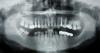

lara Опубликовано 25 февраля, 2008 Поделиться Опубликовано 25 февраля, 2008 Уважаемые стоматологи! Посмотрите, пожалуйста, мой снимок и выскажите свое мнение. 1. Возможна ли имплантация слева и справа, и сколько нужно поставить? Зубов нет более 30 лет, я их не помню.2. Каковы исходы костеобразующих операций на нижней челюсти, всегда ли положительный эффект?3. Каковы результаты имплантации после костеобразующих операций, больше или меньше процент отторжений по сравнению с обычными?4. Можно ли рассчитывать на положительный результат повторной имплантации при отрицательном первичной? На консультации имплантолога еще не была , пока лечу и перелечиваю зубы. Спасибо. Ссылка на комментарий

Большой Зеленый Опубликовано 25 февраля, 2008 Поделиться Опубликовано 25 февраля, 2008 Да у вас тут море кости .Ничего и не понадобится .Сходите на консультацию в доктору.Я думаю все будет хорошо.А зубки надо лечить.В 15 похоже какой то инструмент ... Ссылка на комментарий

Bier Опубликовано 25 февраля, 2008 Поделиться Опубликовано 25 февраля, 2008 если гребень не узкий, то никаких доп. операций не потребуется, по высоте костной ткани явно достаточно. Ссылка на комментарий

Doc Опубликовано 25 февраля, 2008 Поделиться Опубликовано 25 февраля, 2008 А зубки надо лечить.В 15 похоже какой то инструмент ... Не, похоже просто серебряный штифт. Уважаемые стоматологи! Посмотрите, пожалуйста, мой снимок и выскажите свое мнение. 1. Возможна ли имплантация слева и справа, и сколько нужно поставить? Зубов нет более 30 лет, я их не помню.2. Каковы исходы костеобразующих операций на нижней челюсти, всегда ли положительный эффект?3. Каковы результаты имплантации после костеобразующих операций, больше или меньше процент отторжений по сравнению с обычными?4. Можно ли рассчитывать на положительный результат повторной имплантации при отрицательном первичной? На консультации имплантолога еще не была , пока лечу и перелечиваю зубы. Спасибо. 1. Возможна. 3 штуки.2. Не всегда, как всегда и во всем. 3. Процент отторжений от этого мало зависит, куда больше от других фундаментальных факторов.4. Если нет противопоказаний, то можно. Ссылка на комментарий

lara Опубликовано 29 февраля, 2008 Автор Поделиться Опубликовано 29 февраля, 2008 Опять я. Вчера была на консультации имплантолога, доктор сказал, что все возможно, кости достаточно и в толщину. Это приятное. А грустное- удалили мне 28 зуб, сказали, что в жевании участия не принимает, будет мешать имплантир. зубам и затруднять гигиену 27 зуба. Ужасно жалко, с виду был приличный зуб, хотя, может врачи и правы. Теперь к делу. У меня такая ситуация: слева врач собирается ставить Prodigy- 2 имплантата, а справа на шестерку- 1U-implant ( Германия). Доктора, кто-нибудь работал с этими системами, насколько они надежные? На вашем форуме они не на слуху. Для Doca. Почитываю Ваши записки, интересно пишете, респект за прекрасное владение великим и могучим! Ссылка на комментарий